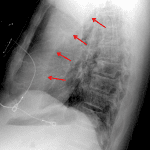

Age: 70

Sex: Male

Indication: Fever

Findings

- Left hilar mass

- Left upper lobe collapse with an aerated portion of the superior segment of the left lower lobe interposed between the atelectatic left upper lobe and the mediastinum (Luftsichel sign)

Diagnosis

- Left upper lobe collapse

Left hilar mass concerning for primary malignancy with associated left upper lobe collapse. Recommend chest CT for further evaluation.